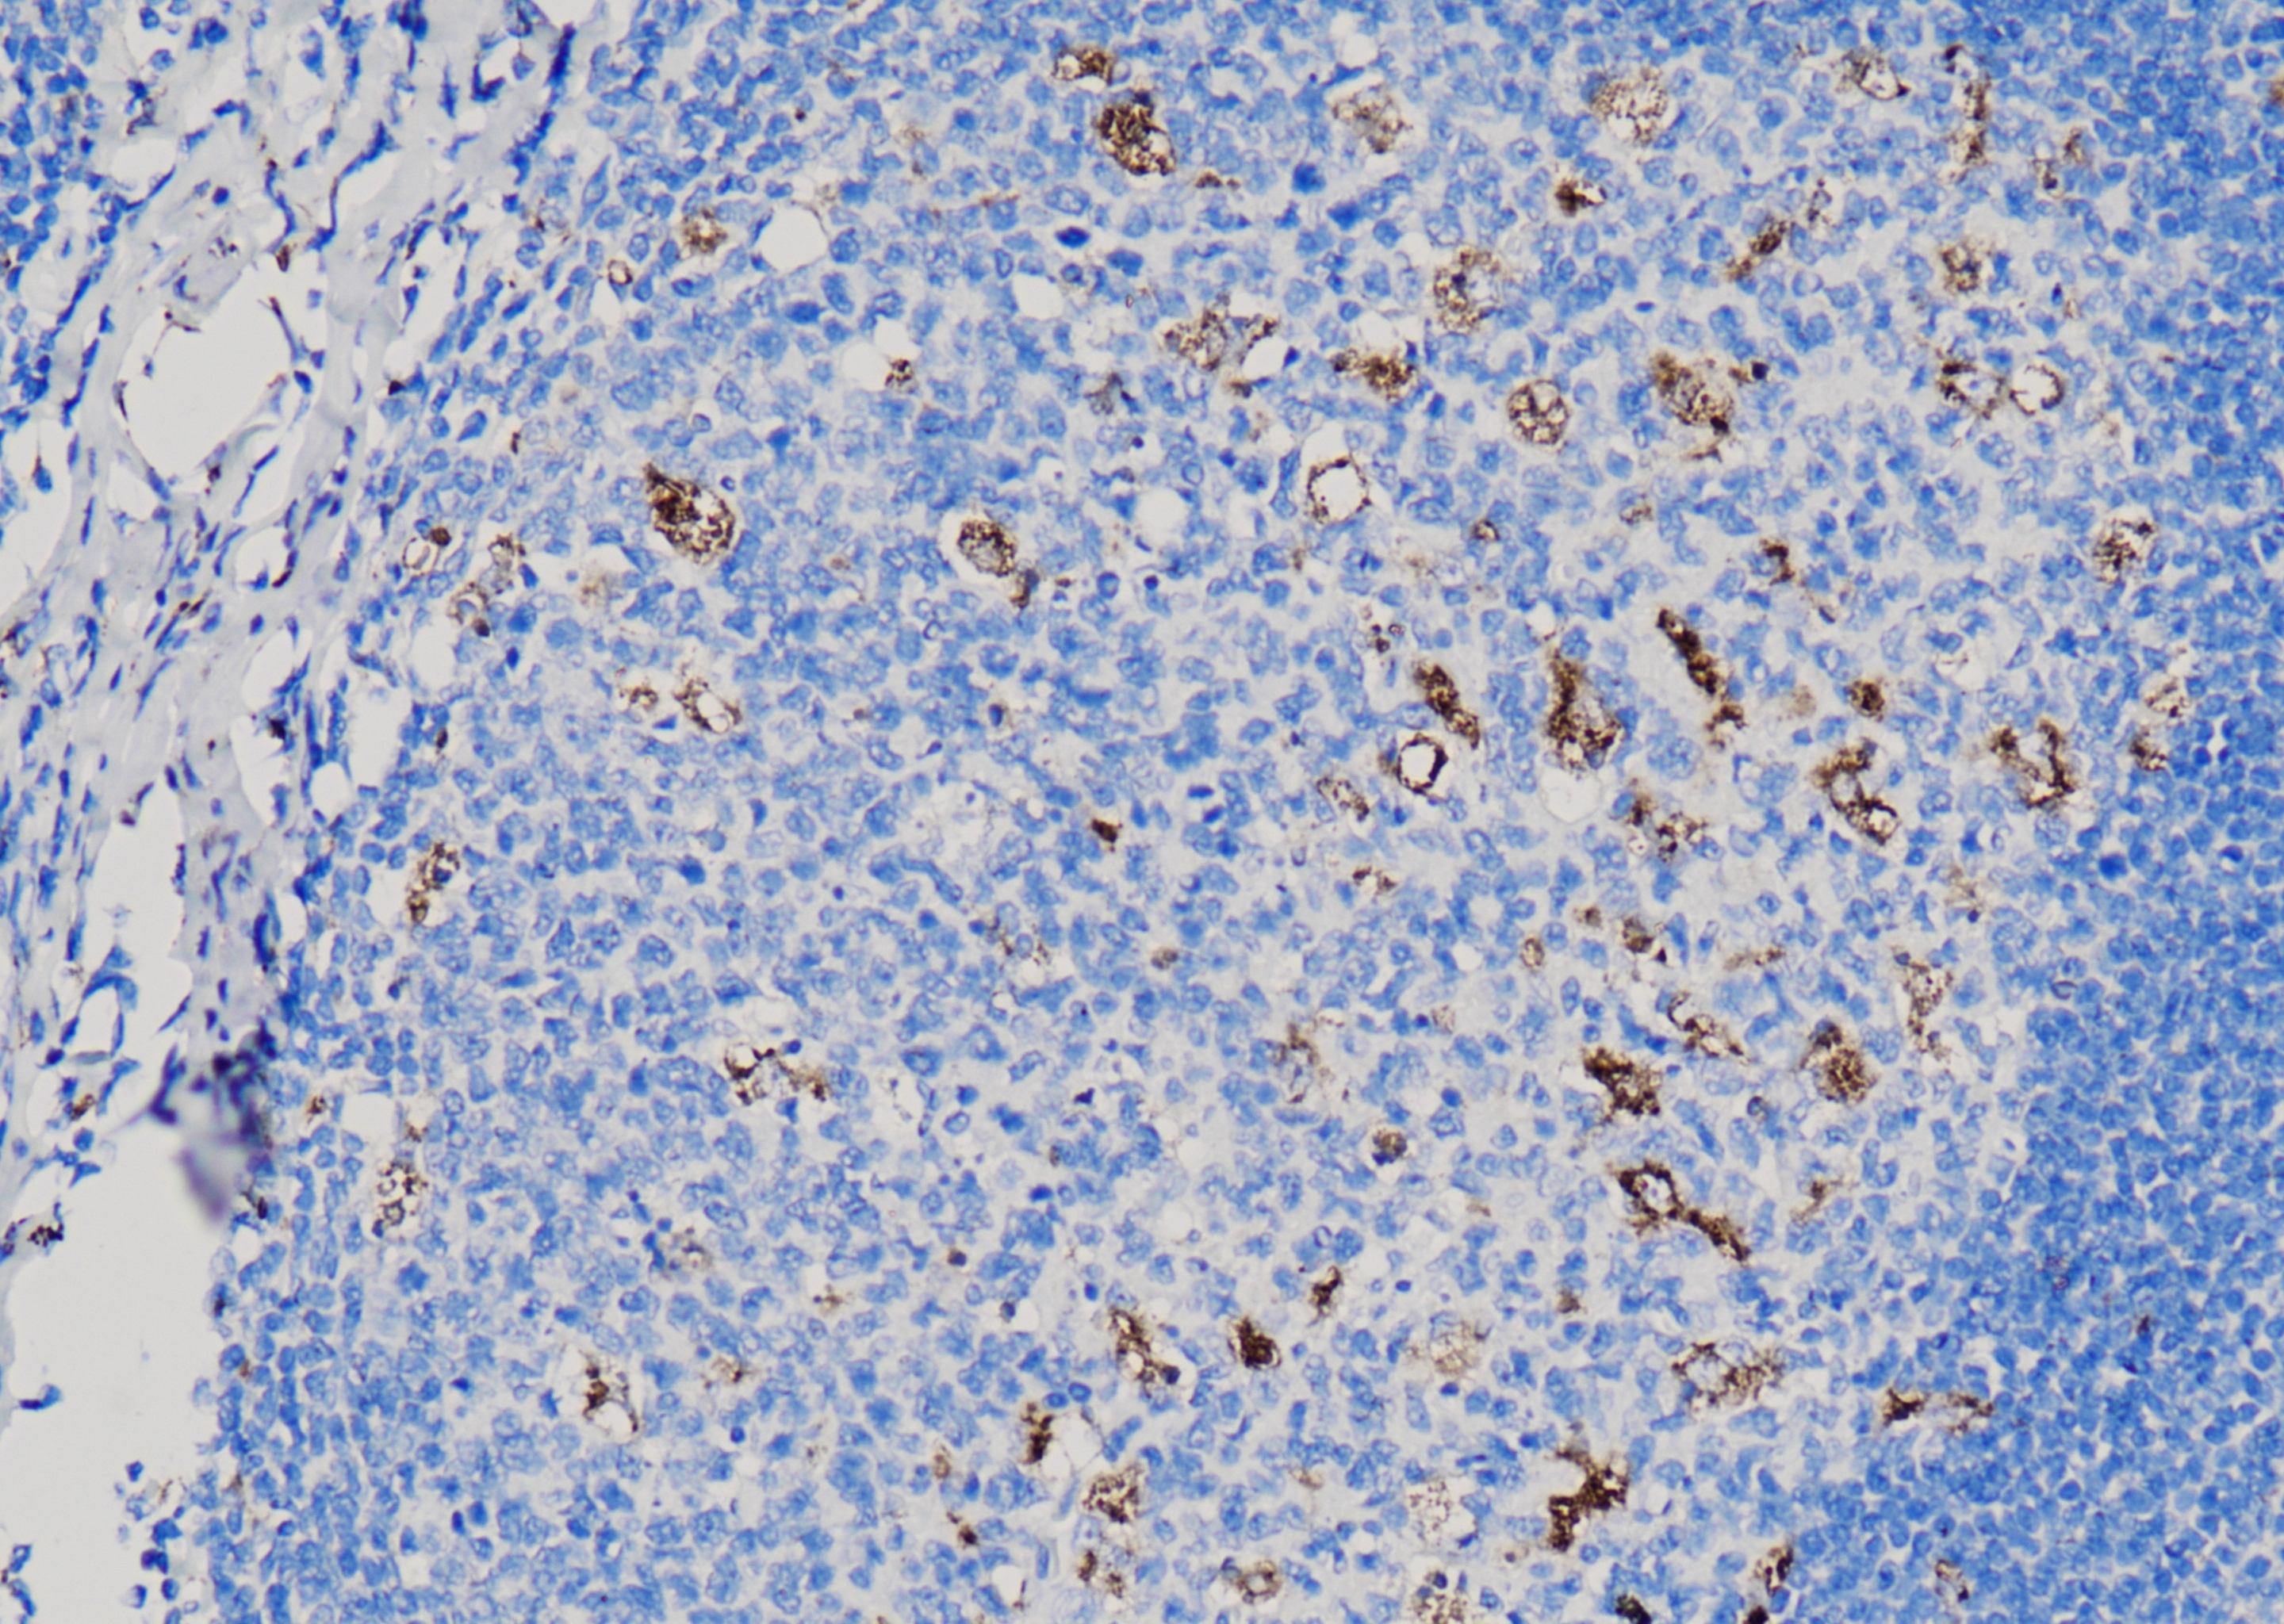

达科为提供200+种IHC一抗产品,有鼠源和兔源两类抗体,手工和仪器均可适配,一抗产品均为单克隆抗体,能够确保与目标抗原结合的特异性,同时一抗具有极高的灵敏度,可以在样本中检测到低表达水平的目标抗原,并获取可靠的结果。